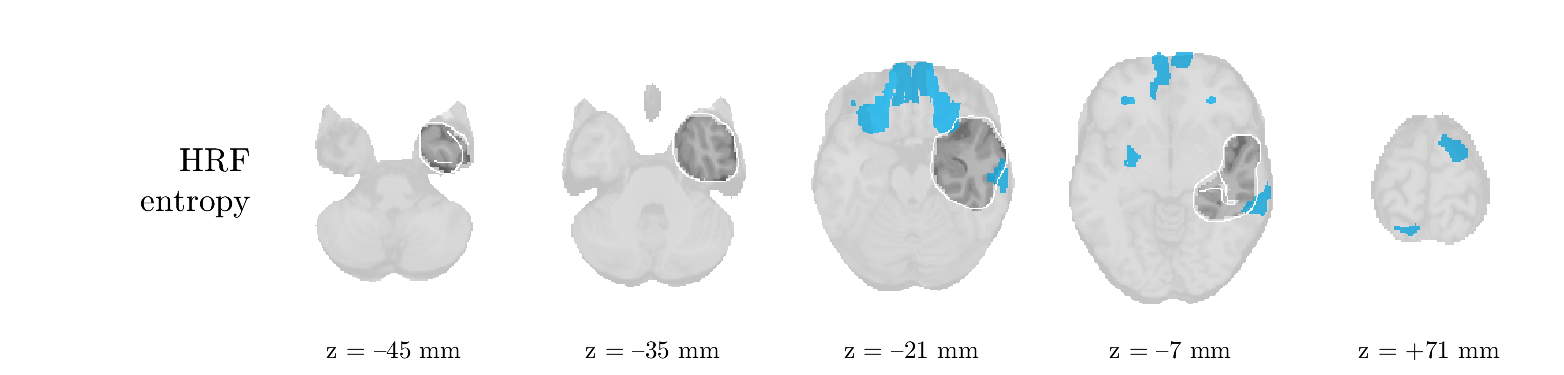

We analyze the solution with sources. Figure 1 shows the EEG signatures and HRF waveforms. One of the sources is highly correlated to the MWF reference (in grey), which was already known from Table B.3. This IED-related source had a typical low-frequency spectrum, which is expected for the typical spike-and-wave interictal discharges. The topography is relatively diffuse, although the highest amplitudes are mostly in the left hemisphere. This is in accordance with the lateralization of ictal onset zone (left temporal lobe, cfr. Table 1). There are some noteworthy observations to be made about some of the other components. The fourth has an unusually sharp spectrum, is mainly localized on two nonadjacent center electrodes, and is sustained for a single period of many seconds Hence, this component likely captured an artifact (of yet unknown origin), although we spotted no large-amplitude changes in the EEG itself. Similarly, the third source is only present at one frontal electrode, and exists in a frequency range above 20 Hz. It might represent a muscle artifact, e.g., due to frowning or twitching of some muscles in the forehead. The HRFs of all ROIs are shown in Figure 1(b). Two of the basis functions seem to have converged to a very similar waveform, which is an unfortunate possibility if two initial HRFs are too close to the same local optimum in their respective parameters. This reduces the expressive power of the basis set, which is clearly visible, since many ROIs have a nearly identical HRF. One of the twenty ROIs with the highest-entropy HRF overlapped the IOZ, although clearly this HRF (bold line) is not among the most dissimilar waveforms for this patient. This is also visible in Figure 2: both the HRF entropy and extremity maps show a small overlap with the delineated IOZ. Despite the good correspondence in the EEG domain, no significant (de)activation of the IED-component is found inside the IOZ.

We analyze the solution with sources, and show the results in Figure 3 and 4. As for patient 1, we found a source which is strongly correlated to the MWF envelope, and which had a mostly low-frequency behavior characteristic for spikes. The topography is mostly uninformative, and does not clearly correspond to the patient’s clinical data. The third source is mostly present at both sides of the head, is very sparsely active in time, and has a high-frequency content: this is most likely an artifact due to the neck muscles. Again, there is one of the highest-entropy HRFs which belongs to a ROI in the IOZ. Now, the waveform is clearly resolved from the other HRFs, through the strong initial dip (before 0 seconds). Such a dip is sometimes observed in HRFs, but its underlying physiological mechanism is not yet fully understood. It is possible that this dip reflects altered vascular autoregulation near the IOZ (cfr. the explanation in the Section 1 of the main text), or a rapid depletion in oxygen due to IED generation (before the IED becomes visible on the EEG). Figure 4 furthermore shows that the IED-related component is significantly active in parts of the IOZ, and deactive in others. As mentioned earlier, this deactivation may or may not be due to errors in sign correction. Interestingly, the ROI with the high alteration in neurovascular coupling is distinct from both the activated and deactivated ROIs.

We analyzed the solution with sources, and show the results in Figure 5 and 6. There is one source which is mostly correlated to the reference (but not extremely, see also Table B.3). This source had a right-temporal focus, conform the diagnosis in Table 1. The second source illustrates the phenomenon of an erroneous sign exchange between the spatial and spectral profiles. Also one of the HRFs has a negative polarity, which is a failure of the sign correction procedure (in this case, because there is exceptionally no positive overshoot). However, the HRF variability metrics are still interpretable, and indeed two ROIs among the ones with the highest-entropy HRFs overlap with the IOZ. The IED component is significantly active in a tiny portion of the IOZ (cfr. Figure 6). The second source is significantly active in symmetrical parts of the parietal lobe. Given its ongoing fluctuation over time, we hypothesize that this source captures a resting state network (RSN).

We analyze the solution with sources, and show the results in Figure 7 and 8. There is a clear IED-related component, with a very high correlation to the MWF reference, a typical spectrum, and an anterior-temporal focus, which corresponds very well to the patient’s diagnosis (cfr. Table 1). The fifth source seems present at only one channel, and has spectral harmonic at Hz and Hz. One of these peaks is reminiscent of the fourth component in patient 1. As Figure 8 shows, the HRF entropy and extremity prove to be strong biomarkers for the IOZ in this case, and also the significant IED activation and deactivation allow correct localization. In Figure 7, it is clear that some HRFs may still have the wrong sign, which means that the interpretation of ‘active’ and ‘deactivated’ is flipped in those ROIs. Hence, regions of significant deactivation are in fact significantly activated. The fourth source had a significant overlap with the auditory RSN, and its spectrum reveals activity in the band.

We analyze the solution with sources, and show the results in Figure 9 and 10. One source is strongly correlated to the MWF, while the other source is likely an artifact, given its very sparse temporal profile. Both sources coincide at one high-amplitude peak, by which we infer that this is probably an artifactual period in the signal. Indeed, when inspecting the original EEG signals, we found high-frequency muscle artifacts at these times. This source also had no significant activation in its spatial map, which corroborates its non-neuronal origin. The IED-related source had a broader spectrum than most other cases, and an uninformative topography. None of the ROIs with high-entropy HRFs is located in the IOZ. The pseudo t-map provides correct localization of the IOZ, however.

We analyze the solution with sources, and show the results in Figure 11 and 12. We found a clear IED-related component, with a characteristic spectrum and a topography which is backed up by the patient’s diagnosis (left anterior-temporal IOZ). The fourth source has a very similar topography and spectrum to the fifth source in patient 5. One HRF inside the IOZ had a high-entropy, and is distinguishable from the others by its very sluggish waveform, i.e., it is smeared out in time, with no sharp over- or undershoot. Also the pseudo t-map provided an accurate localization of the IOZ. Notably, in this patient, the extremity metric misses the deviating HRF in the IOZ (while the entropy metric picks it up). The second source overlapped with the frontal part of the default mode network (DMN), and is active in the and low bands.

We analyze the solution with sources, and show the results in Figure 13 and 14. We found two components which had correlated time courses. At the time of the peaks, we found higher-amplitude events in the EEG with dubious origin, hence they may or may not be artifacts. One of both components is more strongly correlated to the MWF, and its activation is concordant with the IOZ. The second component shows high overlap with the sensorimotor network. For this patient, none of the IOZ’s ROIs had extreme values of either HRF metric.

We analyze the solution with sources, and show the results in Figure 15 and 16. In this patient, there is only a moderate correlation of a component with the MWF reference time course. This component’s topography (left occipital) agrees with the clinical description, however. The HRF extremity (and not the entropy) is high in a small part of the IOZ. Both the significant IED activation and deactivation allow correct localization as well. The second source seemingly captured high-frequency oscillatory activity in the sensorimotor network, similar to the previous patient.

We analyze the solution with sources, and show the results in Figure 17 and 18. The IED-related source had a high correlation with the MWF reference, but an odd bimodal spectrum. Its EEG topography is very consistent with the clinical description. Both HRF extremity and entropy are useful biomarkers for the IOZ. The IED activation and deactivation maps each had a very small overlap with the IOZ. The second source is temporally sparse and captures high-frequency EEG variations, which we identified as muscle artifacts.

We analyze the solution with sources, and show the results in Figure 19 and 20. Again we observe an IED-related source and a seemingly artifactual source with a spectral peak near 34 Hz. Many of the high-entropy HRFs are highly noncausal, and are associated to ROIs inside the IOZ. Hence, with both HRF metrics, the highest-scoring ROIs provides good localization of the HRF. While there are no significantly active ROIs in the IOZ, there are several significantly deactivated ROIs, which may indicate that the sign standardization was not done flawlessly (cfr. also some of the negative-peaking HRFs for patient 10). Surprisingly, the second source had one significantly active ROI, which overlaps with the IOZ, but which did not match its EEG topography. Hence, the nature of this source remains ambiguous.